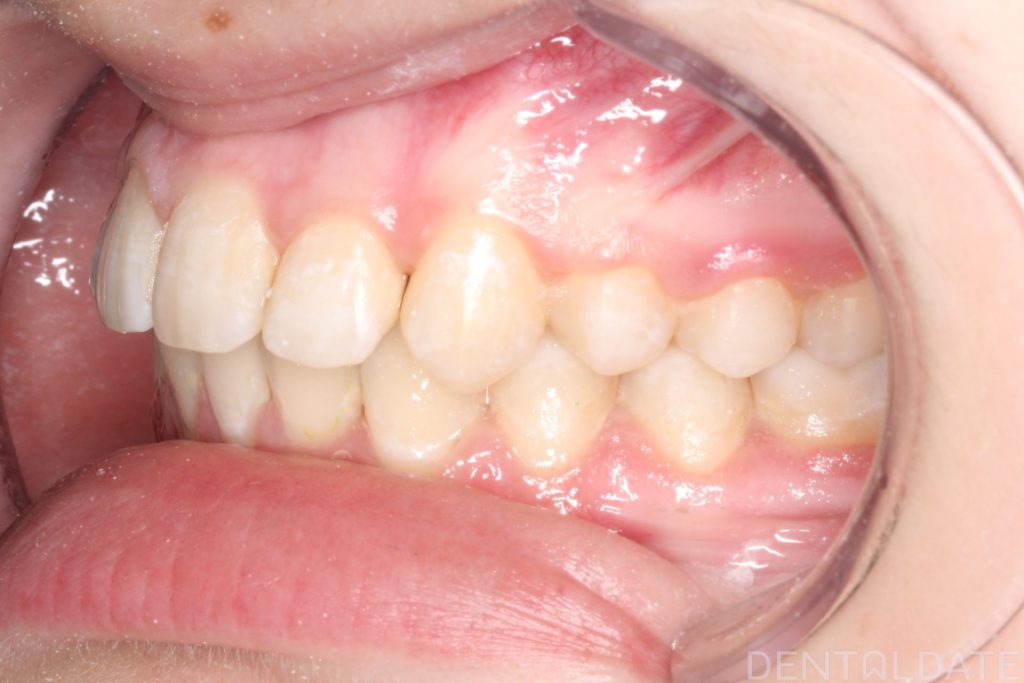

Space for the palatally positioned tooth was created with the use of a mini-screw, the shape of the dental arches was normalized, and the position of the teeth was corrected.